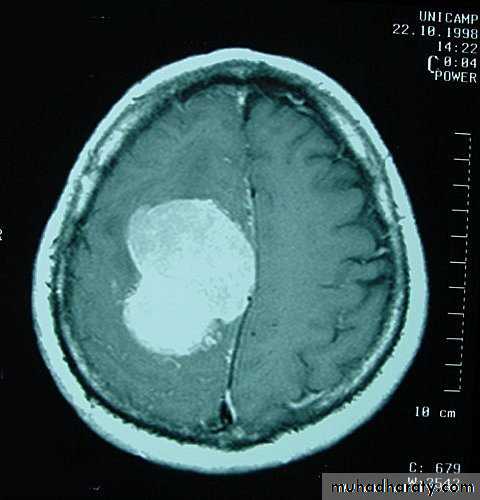

Metastatic Brain Tumours

Metastatic Brain Tumours Pre contrast CT

Metastatic Brain Tumours Post contrast CT